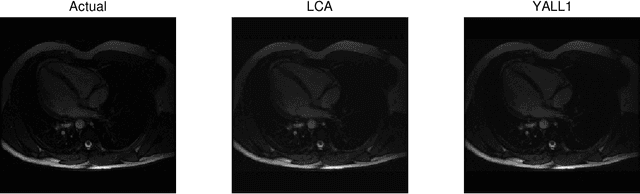

Abstract:Recent research has shown that performance in signal processing tasks can often be significantly improved by using signal models based on sparse representations, where a signal is approximated using a small number of elements from a fixed dictionary. Unfortunately, inference in this model involves solving non-smooth optimization problems that are computationally expensive. While significant efforts have focused on developing digital algorithms specifically for this problem, these algorithms are inappropriate for many applications because of the time and power requirements necessary to solve large optimization problems. Based on recent work in computational neuroscience, we explore the potential advantages of continuous time dynamical systems for solving sparse approximation problems if they were implemented in analog VLSI. Specifically, in the simulated task of recovering synthetic and MRI data acquired via compressive sensing techniques, we show that these systems can potentially perform recovery at time scales of 10-20{\mu}s, supporting datarates of 50-100 kHz (orders of magnitude faster that digital algorithms). Furthermore, we show analytically that a wide range of sparse approximation problems can be solved in the same basic architecture, including approximate $\ell^p$ norms, modified $\ell^1$ norms, re-weighted $\ell^1$ and $\ell^2$, the block $\ell^1$ norm and classic Tikhonov regularization.